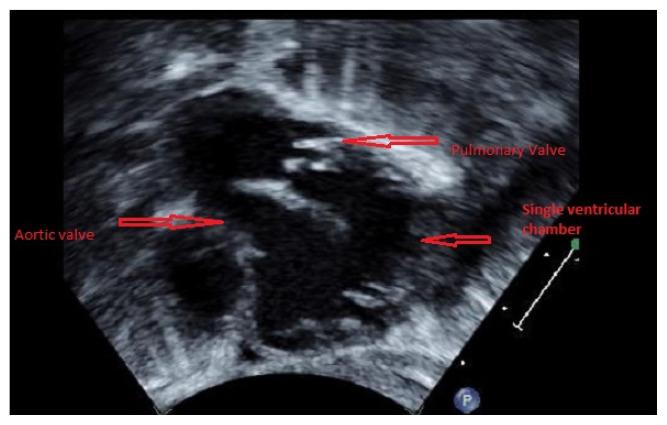

Uncommon Association of Aortopulmonary Window in a Patient with Complex Univentricular Heart and CHARGE Syndrome.

Kans J Med. 2021 Feb 12;14(1):48-50. doi: 10.17161/kjm.vol1414591. eCollection 2021.